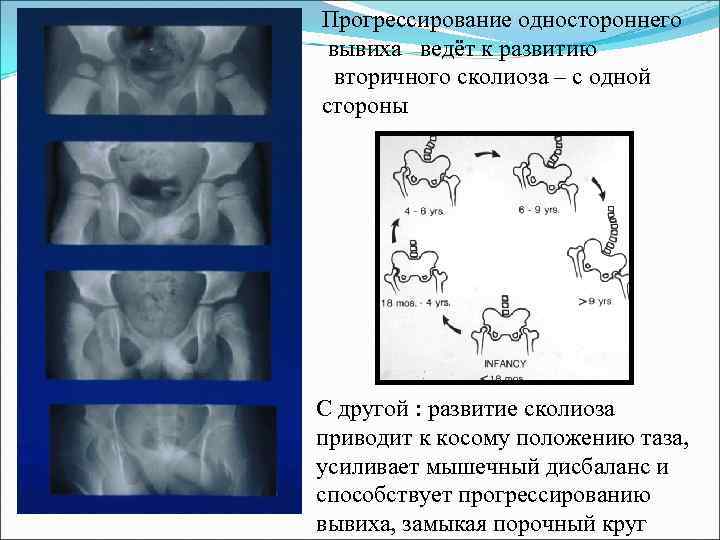

Прогрессирование одностороннего вывиха ведёт к развитию вторичного сколиоза – с одной стороны С другой : развитие сколиоза приводит к косому положению таза, усиливает мышечный дисбаланс и способствует прогрессированию вывиха, замыкая порочный круг